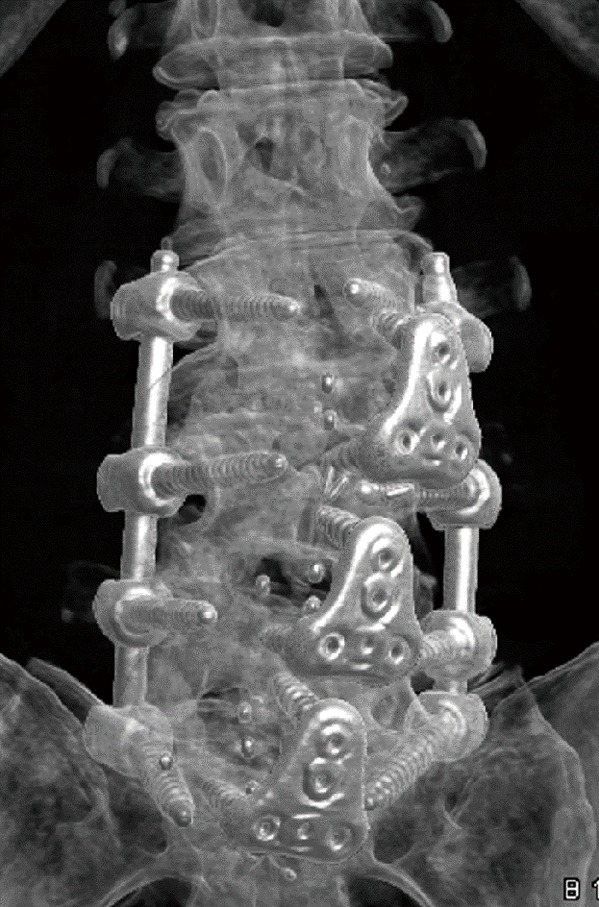

Integrated plate-cages (Independence®, Globus Medical, Inc., Audubon, PA, USA) or separate impacted polyetheretherketone (PEEK) ALIF cages (Perimeter®, Medtronic, Inc., Memphis, TN, USA) plus anterior titanium buttress plates (Pyramid®, Medtronic, Inc.) (Figure 4) were used, depending on the patient’s anatomy. The standalone cages were loaded using the anterolateral attachment hole to the inserter. They were initially inserted obliquely from the left side (at an angle of approximately 30 degrees); midway through insertion, the inserter was rotated laterally to orient the cage to the midline. The integrated plate-cages were loaded straight, impacted obliquely from the left side, and then midway through insertion, the inserter was rotated medially to orient the cage to the midline. All cages were filled with recombinant human bone morphogenetic protein applied to an Absorbable Collagen Sponge (ACS) (Infuse®, Medtronic, Inc.) (9).

Figure 4.

L3–S1 lateral ALIF with PEEK cages and anterior titanium buttress plates and supplemental posterior transpedicular fixation. ALIF, anterior lumbar interbody fusion; PEEK, polyetheretherketone.

Supplemental posterior fixation